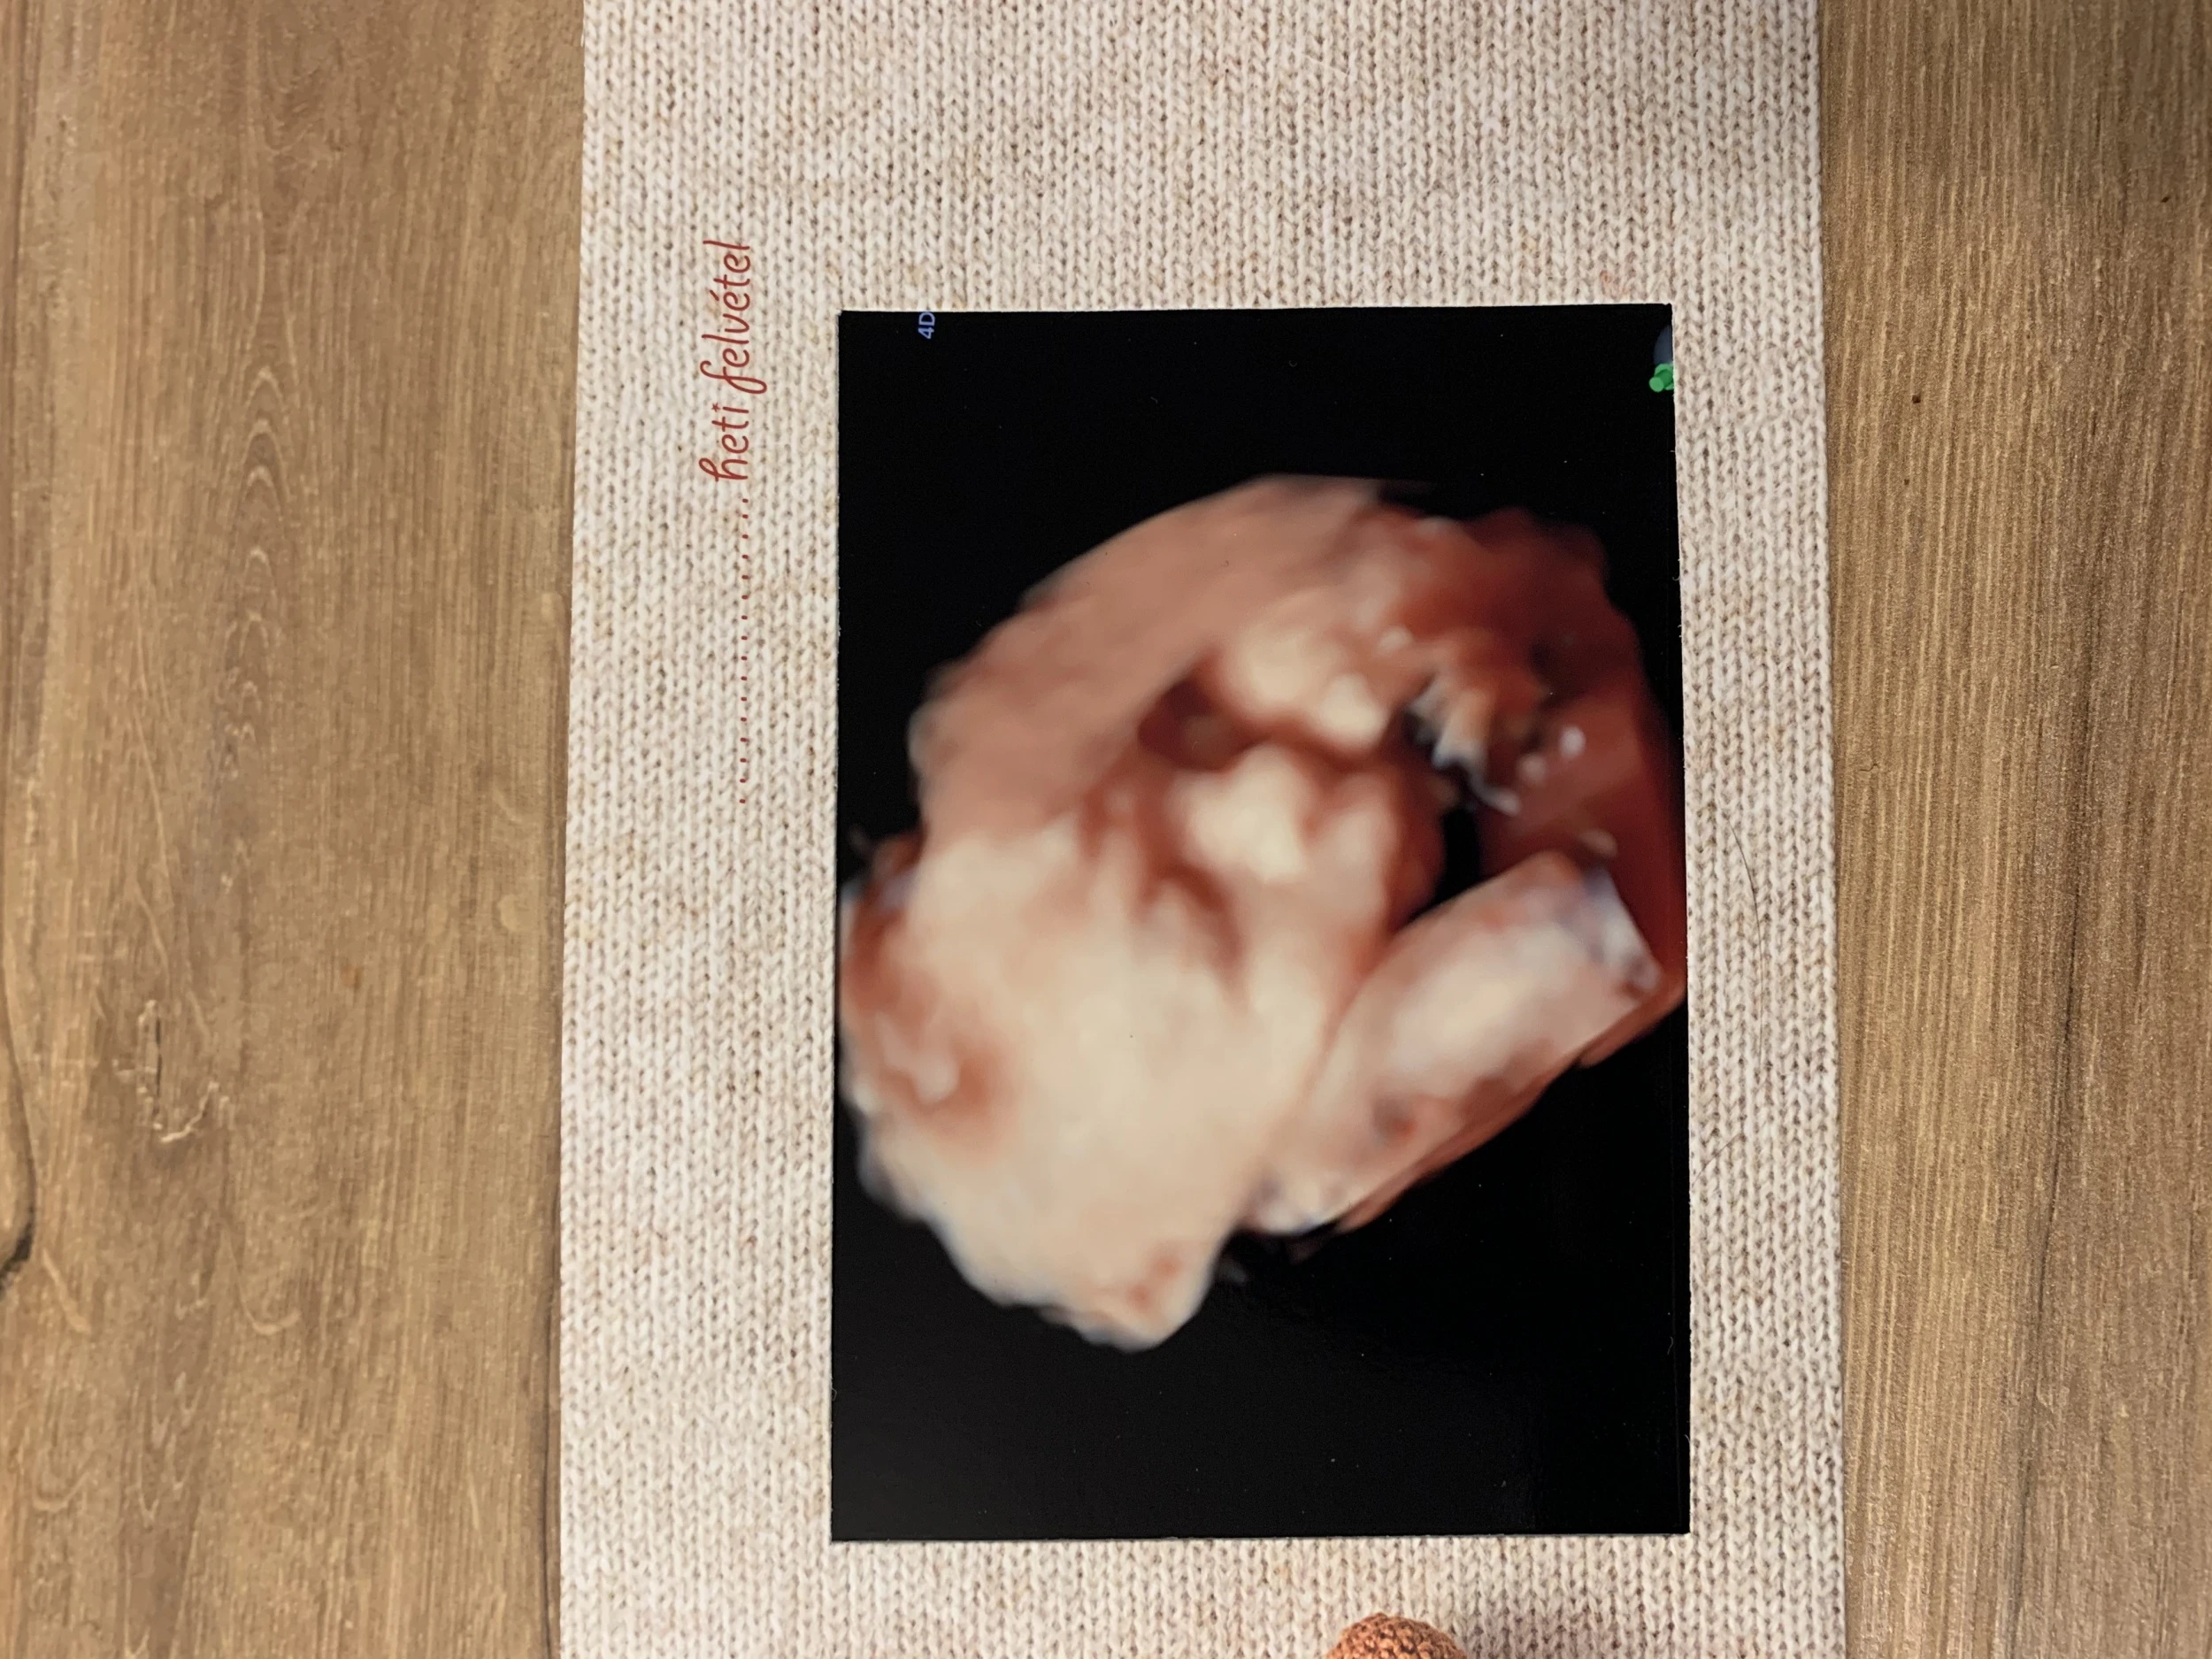

Ideje is volt hazajönnöm, hogy a család és az itthoni barátaim is láthassák élőben ezt a változást. Az ünnepek vészesen közelegnek, ami azt jelenti, hogy nekem még rengeteg intéznivalóm lesz Magyarországon. A szokásos őrült ajándék beszerző körutat igyekeztem a covidra való tekintettel internetes vásárlással megoldani, de az aktuális vizsgálataimon kötelező volt megjelennem. A terheléses cukorvizsgálat már azóta félelmet keltett bennem amióta tisztázódott számomra, hogy ezt el kell végezni a terhességem során. A tűtől való félelmem gyerekkoromból gyökeredzik, amit nem hogy legyőzni, hanem inkább elmélyíteni sikerült az idő múlásával. Sajnos gyakran el is szoktam ájulni utána, ami szintén nem könnyíti meg a helyzetem. Nagyon örültem volna, ha a férjem el tud kísérni, de ez kivitelezhetetlen volt. Bár Magyarországon tartózkodott éppen, hiszen az olasz klub csapata egy magyar együttessel játszott, de ilyenkor a többiekkel kell mozognia és szigorú napirendnek kell eleget tennie. Csak nagyon indokolt esetben kaphatna lehetőséget a távozásra, például szülés esetén, így tudtam, hogy ezt most egyedül kell megoldanom. Nem mondom, hogy nem gyönyörű a Citadella és környéke, de mikor a Bérc utca lankáin besétáltam korán reggel éhgyomorral a magánegészségügyi központ ajtaján, nem tudtam feltétlenül csak erre gondolni. De aztán felülkerekedtem ezeken az érzéseken. Amikor a glükózt tartalmazó löttyöt kellett felhajtanom arra gondoltam, hogy egy elrontott limonádé, ez lelkiekben némiképp segített. Szerencsére miután ez megtörtént nem volt időm sokáig sajnálni magamat, ugyanis időpontom volt ultrahangra. Átsétáltam az emeletre, ahol rögtön szólítottak és már kezdődött is a vizsgálat. Talán az előbb említett események miatt egy kicsit szórakozottan néztem a képernyőt. A vizsgálatot végző szakember először elsorolta az asszisztensének a méreteket, adatokat majd egy gombnyomással váltott és megláttam először 4D-ben a bennem ‘lakó’ kisbaba arcát. Nem  tartom magamat túl érzelgős embernek, de rögtön könny szökött a szemembe. Elképesztő élmény volt, amíg élek nem felejtem el. Az örömömet pár perc után kicsit beárnyékolta, hogy Gergő nem élhette ezt át velem. Természetesen, amint kijöttem az ajtón az első az volt, hogy elküldtem neki egy fotót, illetve még egy pendrive-ot is kaptam a felvétellel, így kicsit megnyugodtam, hogy nem maradt le teljesen az élményről.

tartom magamat túl érzelgős embernek, de rögtön könny szökött a szemembe. Elképesztő élmény volt, amíg élek nem felejtem el. Az örömömet pár perc után kicsit beárnyékolta, hogy Gergő nem élhette ezt át velem. Természetesen, amint kijöttem az ajtón az első az volt, hogy elküldtem neki egy fotót, illetve még egy pendrive-ot is kaptam a felvétellel, így kicsit megnyugodtam, hogy nem maradt le teljesen az élményről.